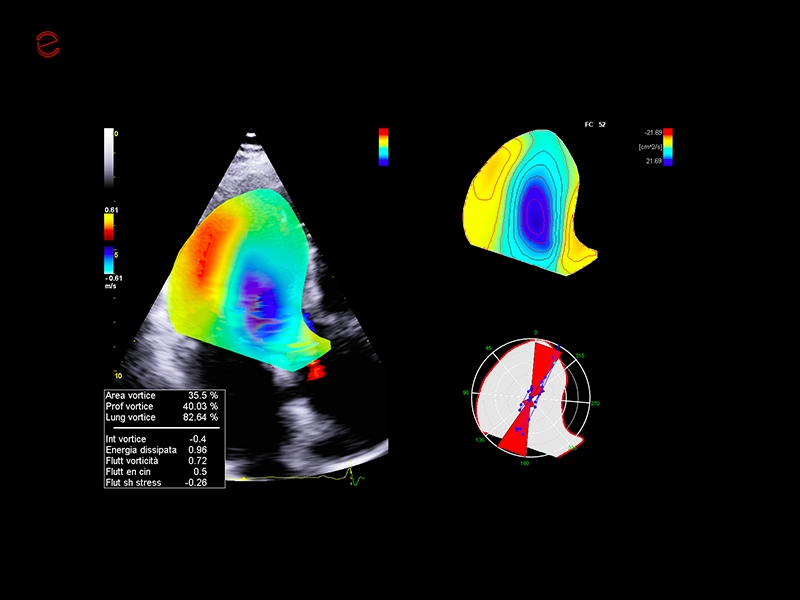

MyLab™X90 - Cardiovascular 03

MyLab™X90 - Cardiovascular 03